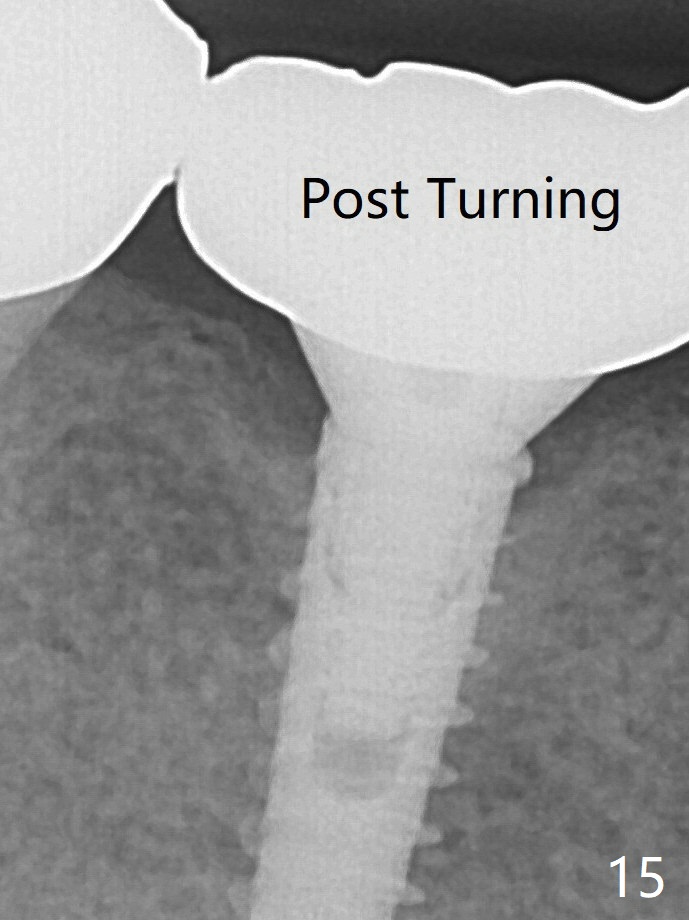

After turning, the abutment appears to be completely seated (Fig.15 (3 years post cementation), as compared to Fig.11 (both bitewing)). 远中间隙还不够,第一基台可能还没有完全被动就位,第二,邻面大一些间隙容易让取模材料进入邻面,包绕牙冠